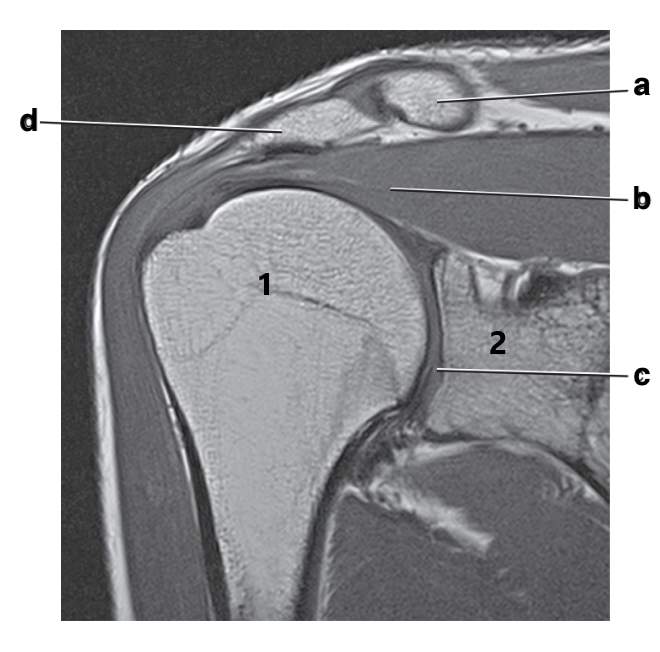

What is letter d?

Acromion

Scapular spine

Supraspinatus tendon

Which of the following is NOT a method to help control access to the MRI environment?

What is letter b?

Supraspinatus muscle

Superior glenoid labrum

Which letter is the talus?

Posterior glenoid labrum

What imaging plane is this?

coronal

What is letter D arrow pointing to?